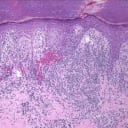

Alle 3 Bilder ansehenEine Stanzbiopsie der linken zweiten Zehe zeigt sowohl ein oberflächliches als auch ein tiefes perivaskuläres entzündliches Infiltrat, das vorwiegend lymphozytär ist, eine oberflächliche Hautblutung und eine lichenoide Gewebereaktion bzw. Interfacedermatitis (Abb. 4-6).

Stanzbiopsie

Grundlage für die Diagnose bildeten die Biopsieergebnisse, die lokale entzündliche Veränderungen (perivaskuläre lymphatische Infiltrate assoziiert mit papillärem Hautödem und epidermaler Spongiose) zeigten, die typisch für primäre Frostbeulen sind. Die Pathophysiologie ist noch kaum verstanden, sie scheint aber mit einer erhöhten kutanen Vasoreaktivität einherzugehen, die zu mikrovaskulären Verletzungen und einer daraus resultierenden Entzündungsreaktion führt.